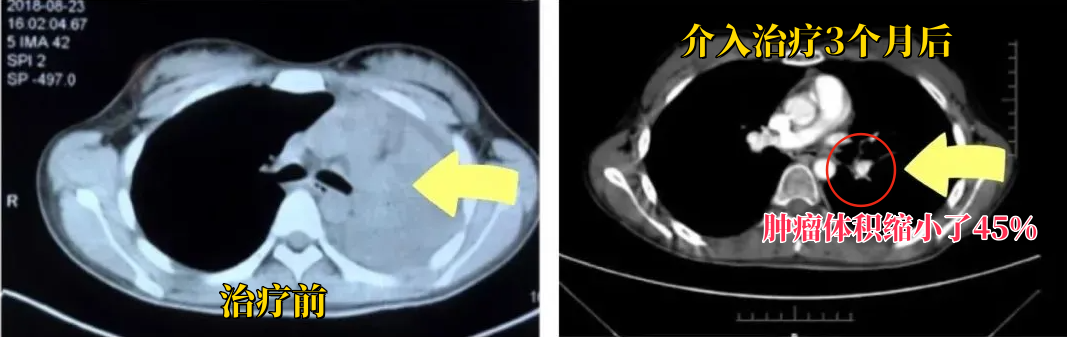

经过周密的术前准备,广州新市医院肿瘤科三区张俊杰主任团队为张先生实施了肺部经皮穿刺肺癌射频消融术治疗。手术过程非常顺利,术后张先生恢复良好,没有出现任何并发症。

更令人惊喜的是,在术后42天的复查中,CT结果显示张先生的肿瘤体积缩小了45%!这个结果不仅让张先生和家人喜出望外,也让广州新市医院肿瘤科三区张俊杰主任团队成员倍感欣慰。